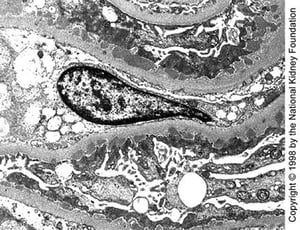

Immune complexes are seen as dense deposits on electron microscopy (see figure Electron Microscopic Features in Immunologic Glomerular Disorders). Subepithelial dense deposits occur with early disease, with spikes of lamina densa between the deposits. Later, deposits appear within the glomerular basement membrane (GBM), and marked thickening occurs. A diffuse, granular pattern of IgG deposition occurs along the GBM without cellular proliferation, exudation, or necrosis.

Medium-sized subepithelial dense deposits are seen on transmission electron microscopy in late stage I disease (×10,200).

Image provided by Agnes Fogo, MD, and the American Journal of Kidney Diseases' Atlas of Renal Pathology (see www.ajkd.org).